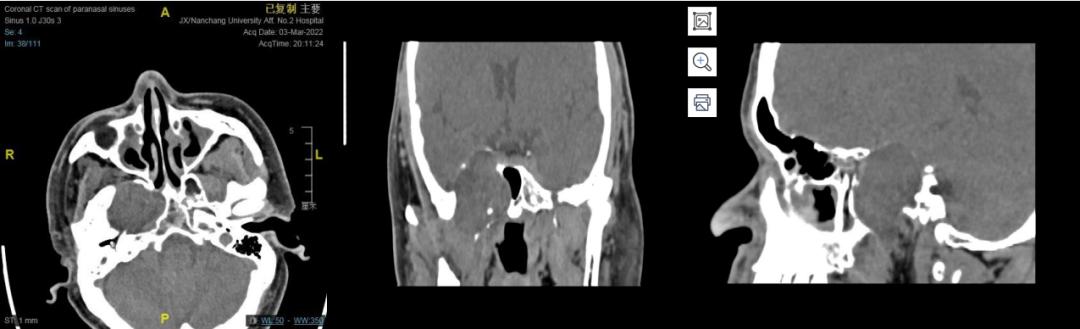

副鼻窦CT平扫

右侧鞍旁见类圆形占位,中央稍低密度,周围环形稍高密度,可见残留骨质密度影,大小约32☓46mm,邻近骨质吸收变薄,建议MRI平扫+增强扫描